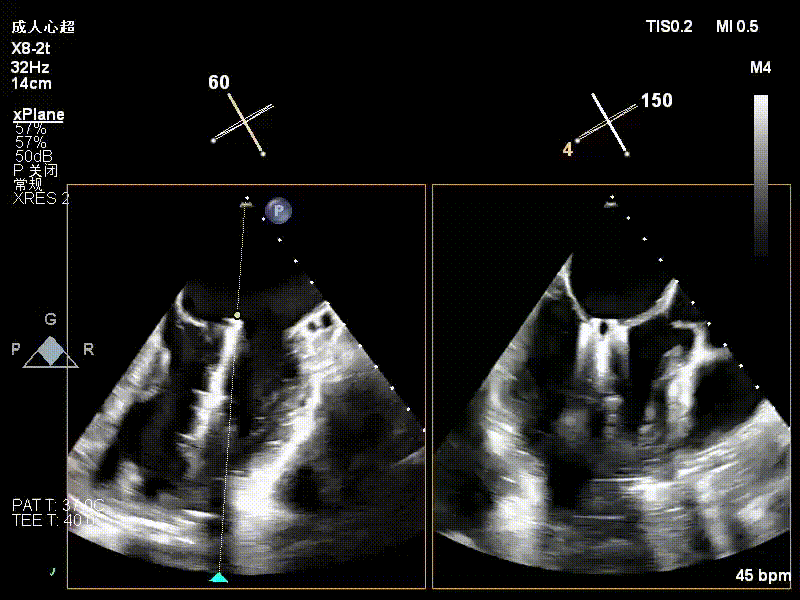

术中超声(关键步骤)

术中超声要点